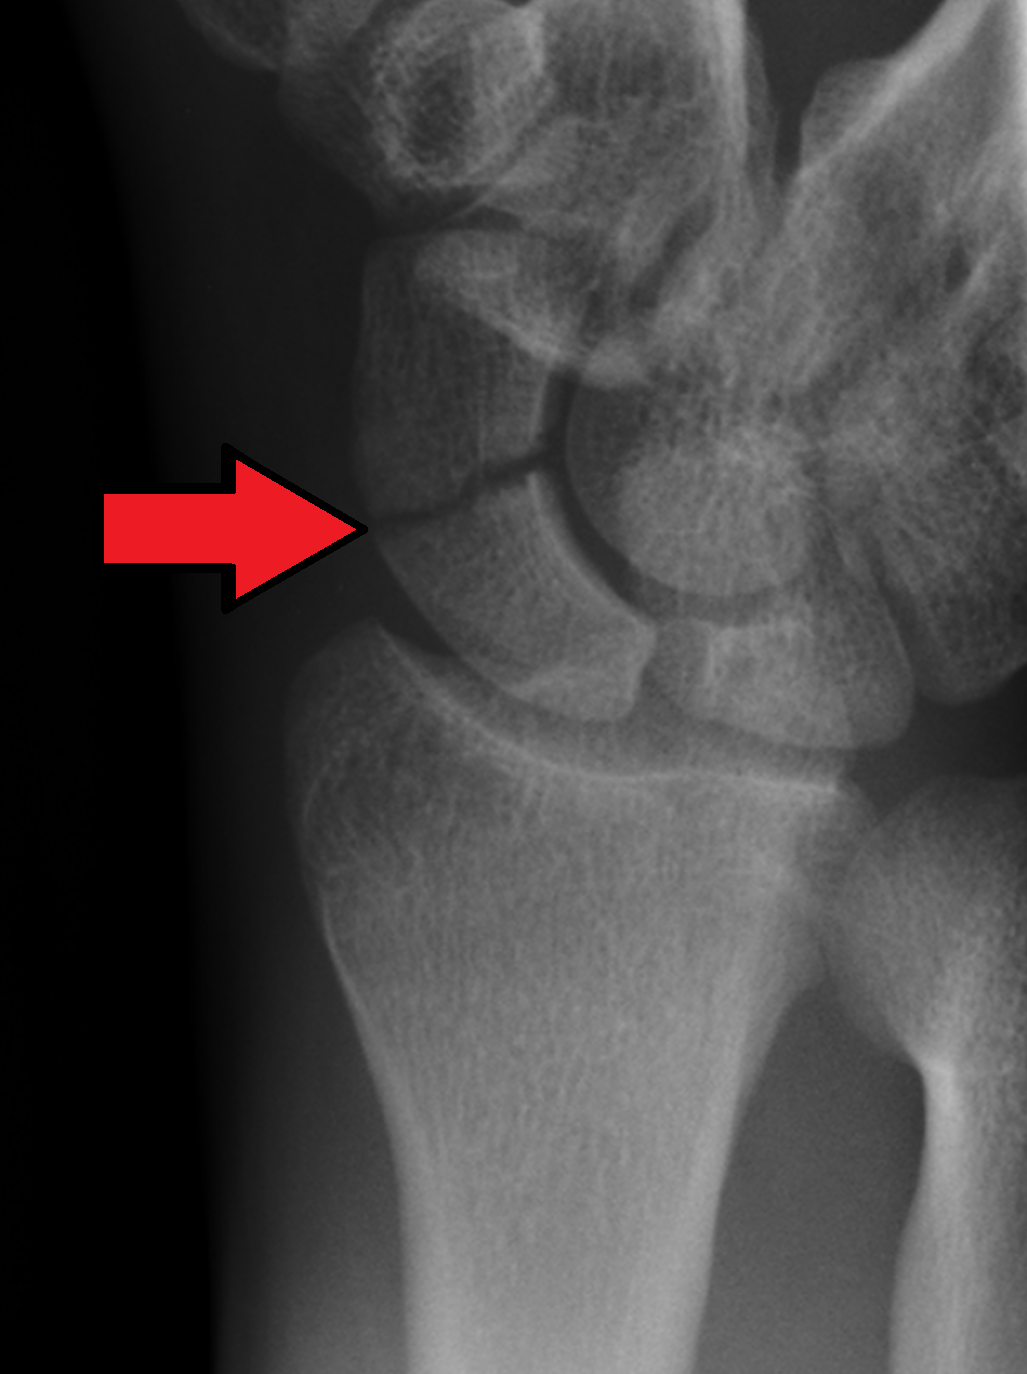

진단은 Anatomical Snuff Box 라고 불리는 부위에 통증이 있으며 주상골을 눌러보았을 때 통증이 있는 경우 임상적으로 진단이 가능하며, 초기 방사선 사진에서는 골절이 보이지 않더라도 반드시 2주 뒤 2차 방사선 사진을 촬영하여야 합니다. MRI 에서 모호한 골절의 경우 2.8일이 경과한 후에 가돌리늄을 이용해 증강시켜 골절을 확인할 수 있습니다. (혈류량을 확인해 볼 수도 있습니다)

주상골 골절의 가장 큰 골치아픈 점은 불유합이나 무혈성괴사 가 발생할 수 있다는 것입니다.

전방부 쪽으로는 : Superficial palmar br. of radial artery 가 20~30% 혈류를 공급하며

후방부 쪽으로는 Dorsal carpal br. of radial a. 가 70~80% 혈류를 공급합니다.

Waist 에서 Proximal에 가까이 골절될 수록 혈행 공급이 줄어들거나 차단이 될 수 있어, 지연유합이나, 불유합, 근위 골절편의 무혈성 괴사를 꼭 의심해보아야 합니다.